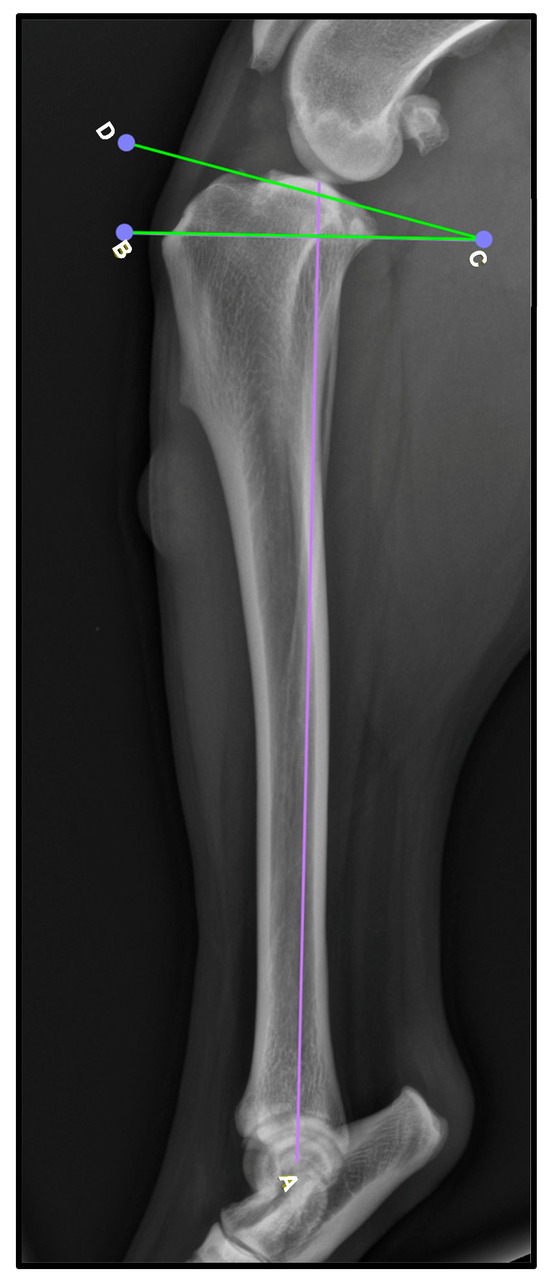

To obtain these measurements, the lateral view was used. To determine the TPA (Figure 1), the mechanical axis of the tibia is drawn by connecting the midpoint of the intercondylar eminence to the center of the talocrural joint [A, Figure 1]. Then, a second line is drawn along the slope of the medial tibial condyle to establish the tibial plateau line [D–C, Figure 1]. Finally, a perpendicular line to the mechanical axis is created [B–C, Figure 1], and the TPA is determined as the angle formed between this line and the tibial plateau line. While TPA was recorded, no statistical analysis was performed to assess its relationship with patellar ligament thickening, as this was not the primary focus of the study.

Figure 1.

Determination of the tibial plateau angle. A: line parallel to the tibial sagittal plane; B–D: line perpendicular to the previous one. The tibial plateau angle is highlighted in green.